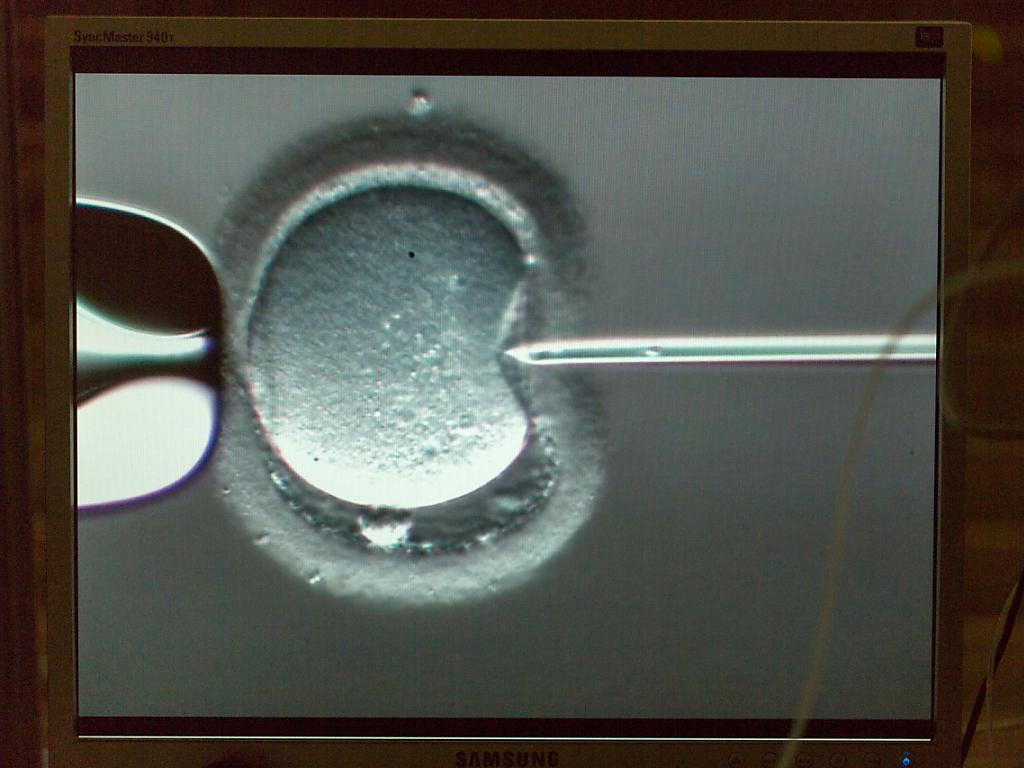

Ein Spermium wird in eine Eizelle injiziert. (Archivbild) KEYSTONE/GAETAN BALLY sda-ats

Jedes dreissigste im Jahr 2021 geborene Kind entstand demnach durch In-vitro-Fertilisation, bei der Labormedizinerinnen und -mediziner ausserhalb des Körpers weibliche Eizellen mit männlichen Spermien befruchten.